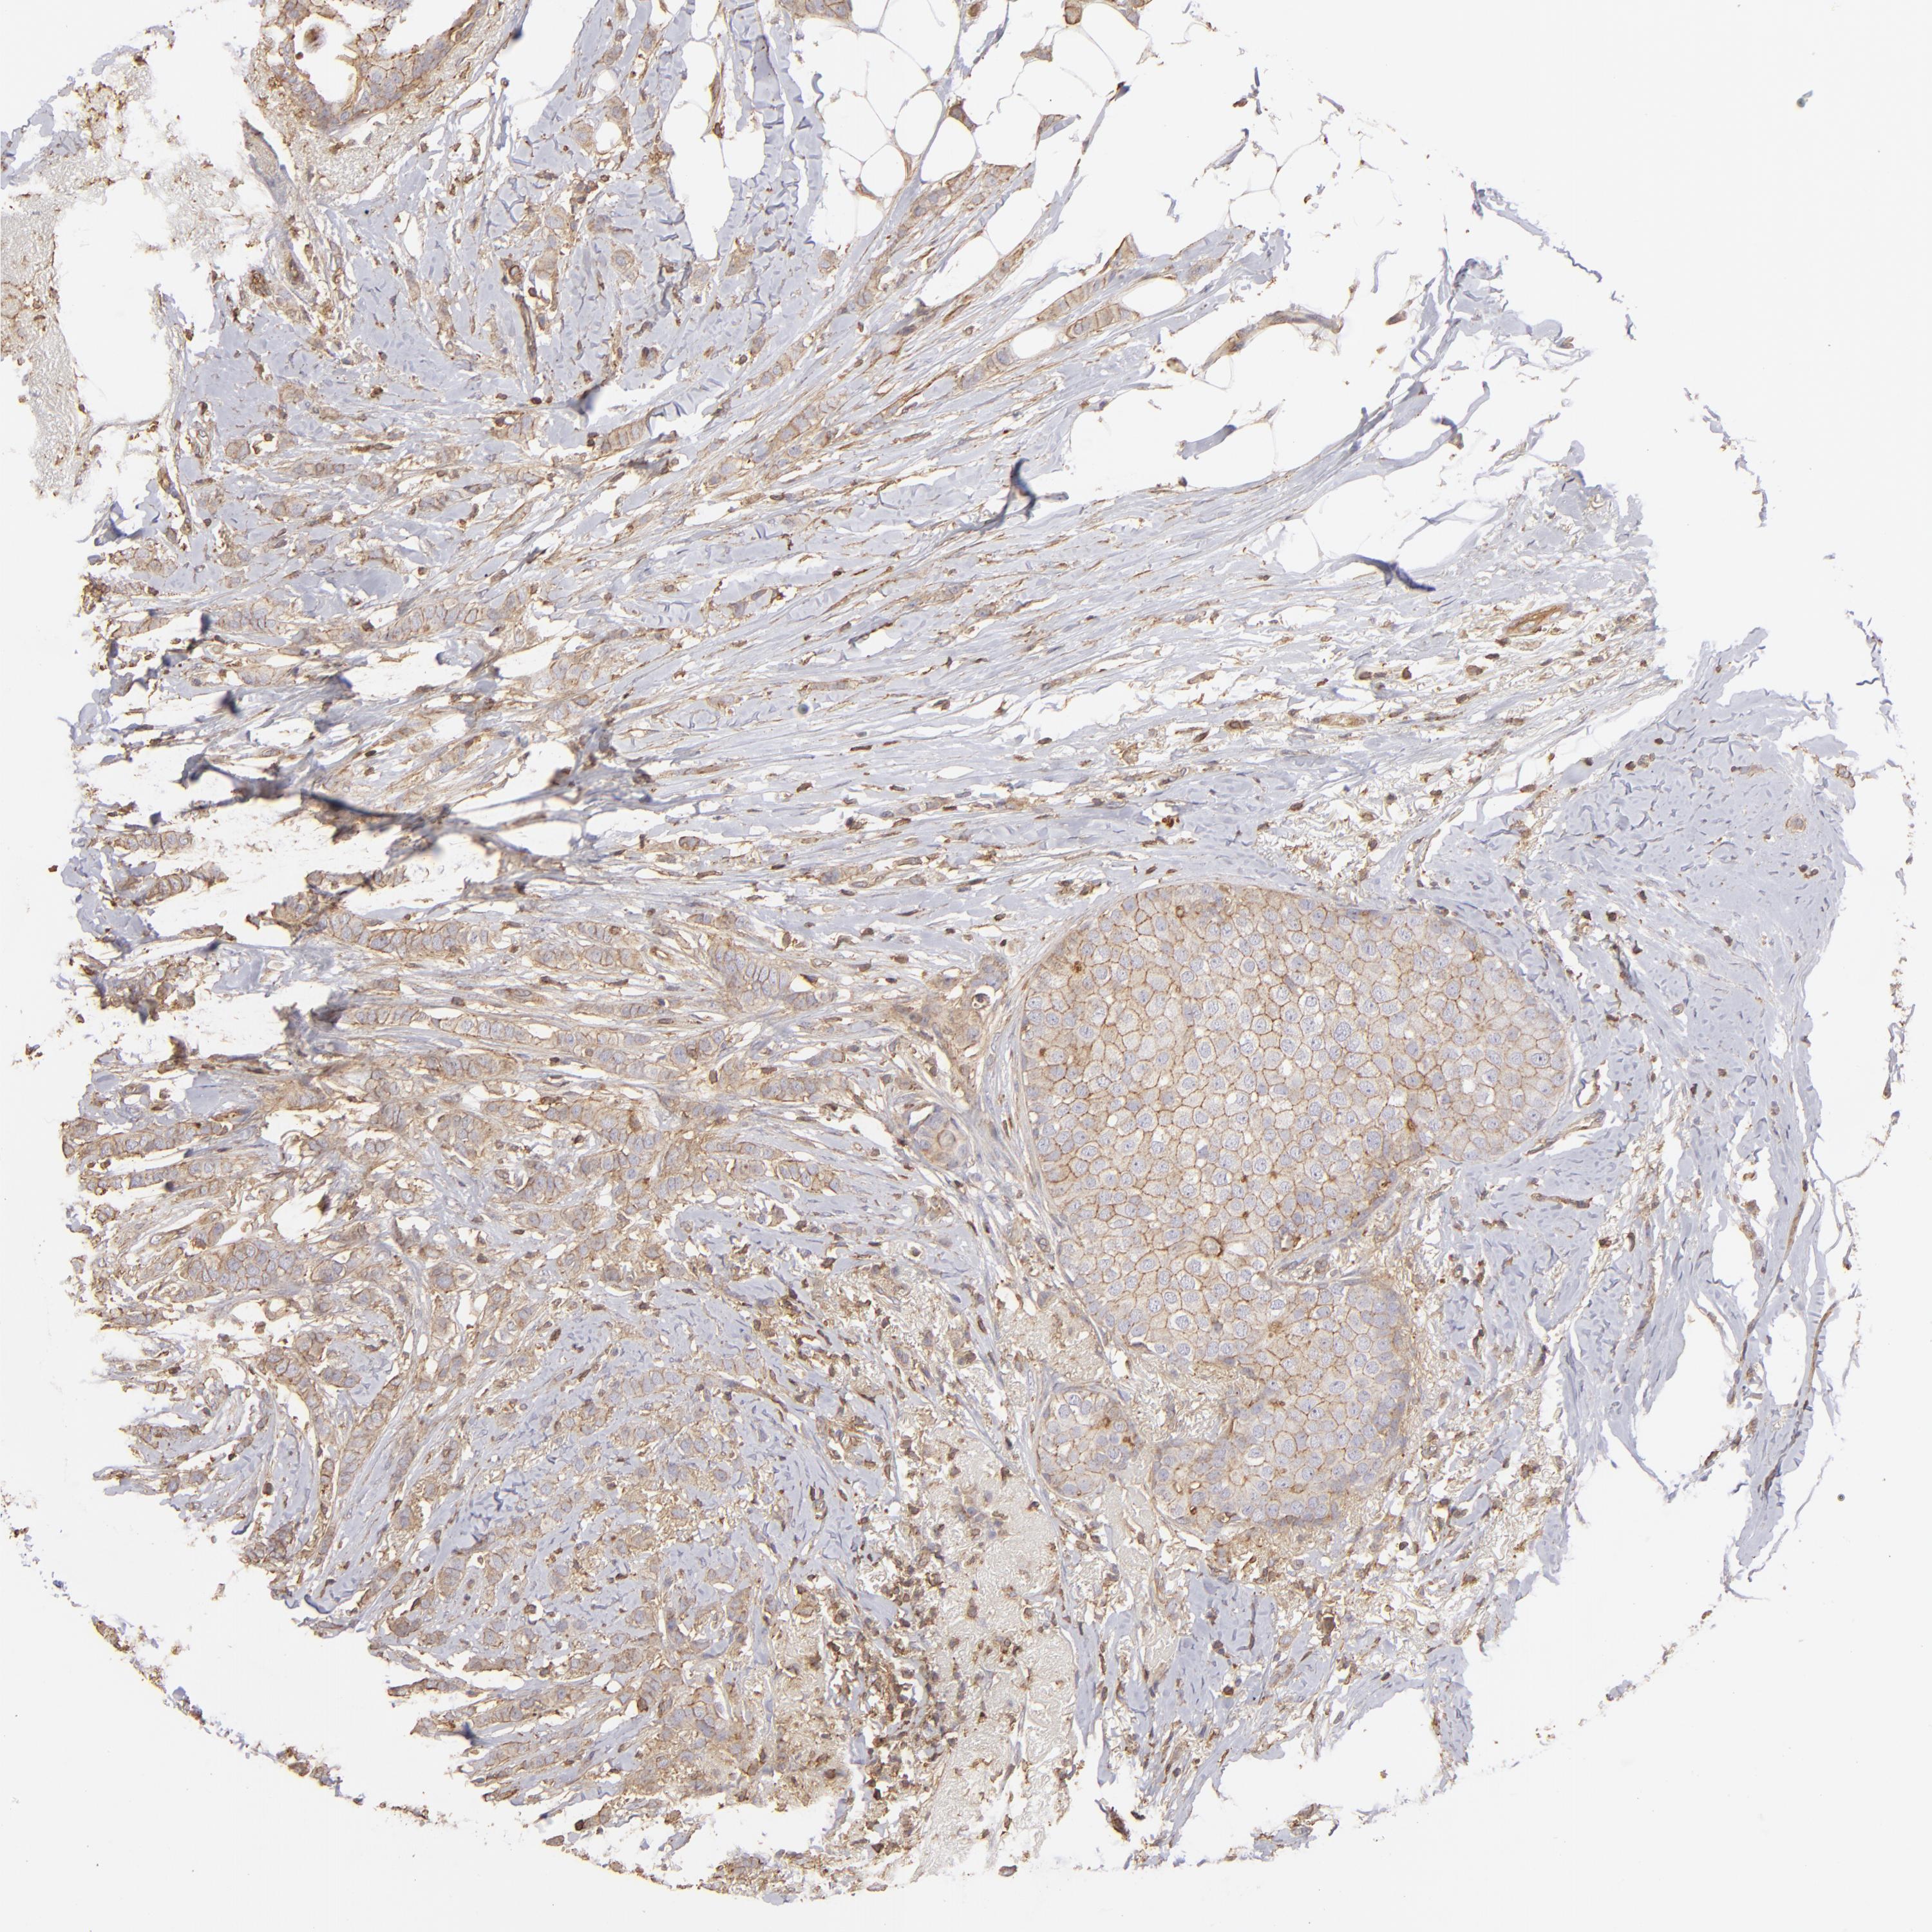

BRCA TCGA BRCA VALIDATION PROTEIN EXPRESSION

ANTIBODIES

AND

VALIDATION